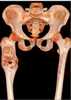

Abnormal proximal femur

The femur (, pl. femurs or femora ), or thigh bone, is the proximal bone of the hindlimb in tetrapod vertebrate, the largest bone of the human body. [Source: Wikipedia ]